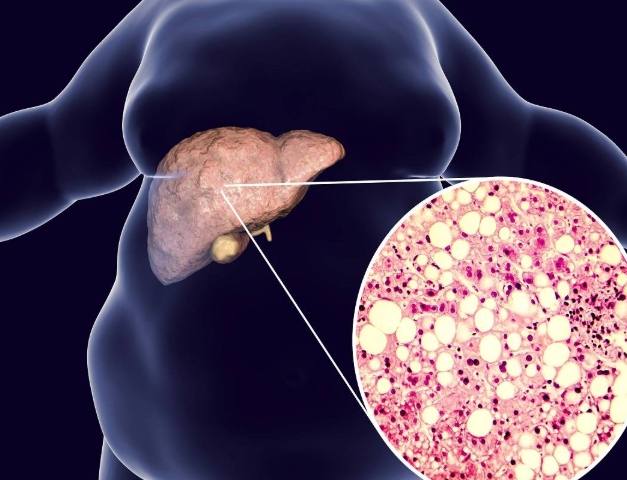

為什麼要知道自己的脂肪肝指數?因為脂肪肝現在太普遍了,幾乎成了現代人的國民病。但很多人覺得它不痛不癢,就放著不管。這其實很危險,脂肪肝是肝臟發炎、纖維化,甚至演變成肝硬化的前期階段。

我記得醫生跟我說,超音波雖然可以直接看到脂肪肝(肝臟看起來亮亮的),但那是一種比較主觀的分級(輕、中、重度)。而脂肪肝指數給的是一個具體數字,方便追蹤變化。

如果指數大於等於60,那就是紅燈了。強烈建議去找腸胃肝膽科醫生報到,做個超音波看清楚肝臟的狀況。這時候肝臟很可能已經有明顯的脂肪浸潤。

有個常見的迷思要打破:脂肪肝指數正常,不代表一定沒有脂肪肝。反之,指數超標,也未必100%有脂肪肝。這些指數是「預測模型」,不是診斷工具。最終的診斷還是要靠超音波等影像檢查。但指數異常絕對是一個必須正視的強烈信號。